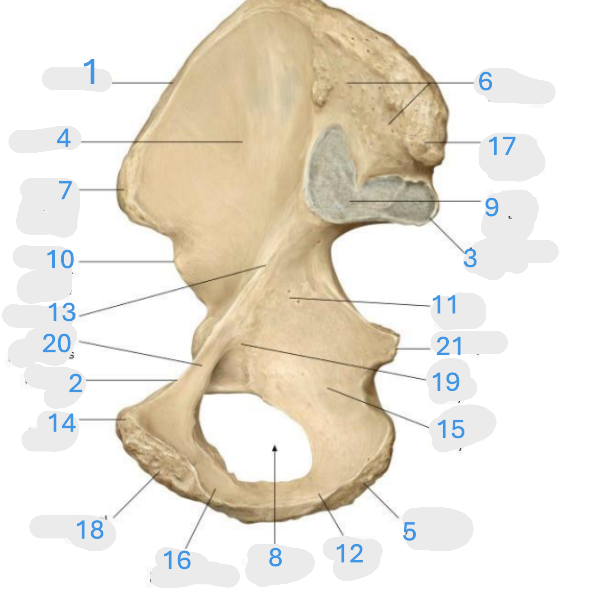

Where is the iliac crest

1

Where is the pectineal line

2

Where is the posterior iliac spine

3

Where is the iliac fossa

4

Where is the ischial tuberosity

5

Where is the iliac tuberosity

6

Where is the anterior superior iliac spine

7

Where is the obturator foramen

8

Where is the auricular surface of the ilium

9

Where is the anterior inferior iliac spine

10

Where is the ilium body

11

Where is the ischial ramus

12

Where is the arcuate line

13

Where is the pubic tubercle

14

Where is the ischium body

15

Where is the inferior pubic ramus

16

Posterior superior iliac spine

17

Where is the symphyseal surface

18

Where is the pubis body

19

Where is the superior pubic ramus

20

Where is the ischium body

21